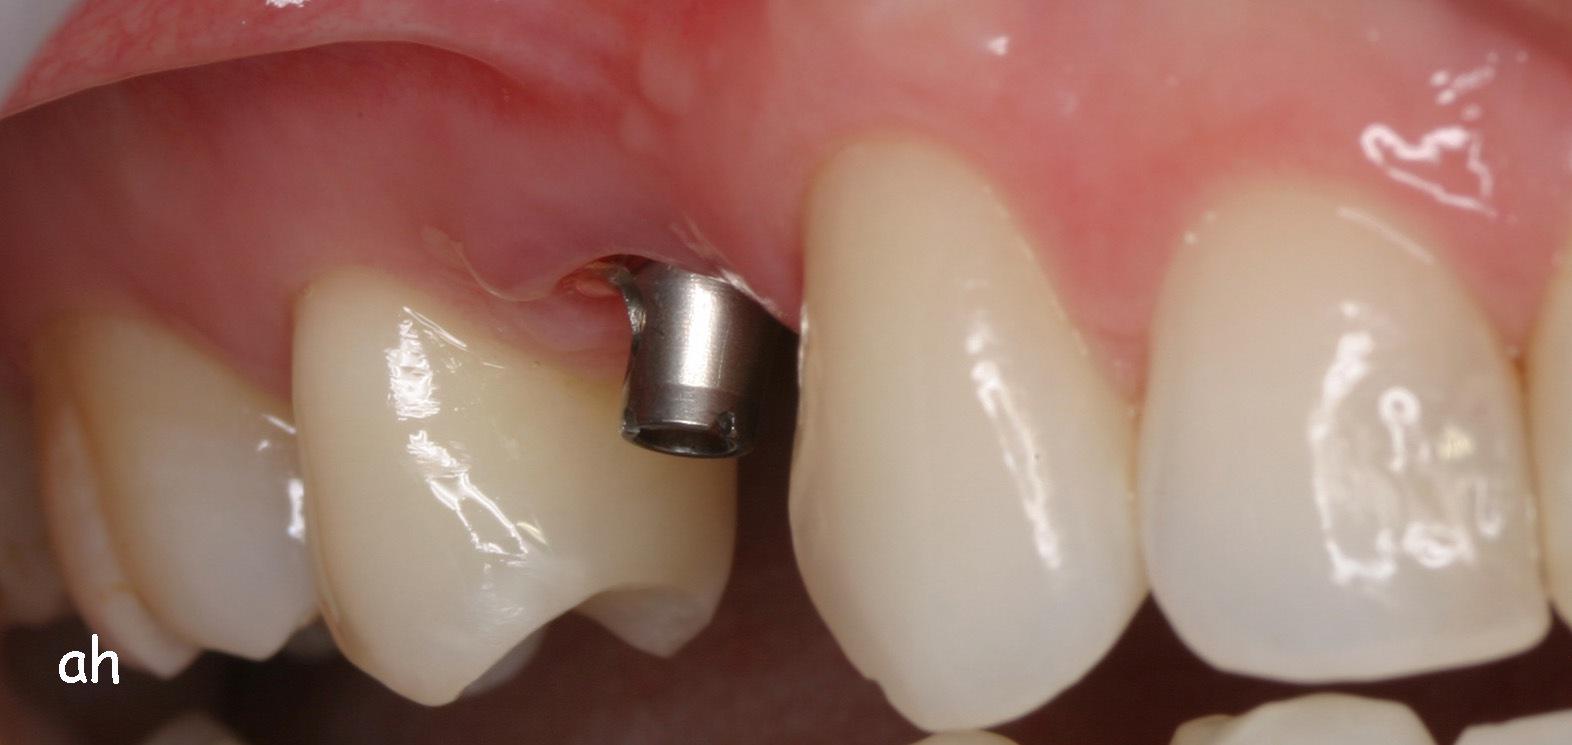

Exemple 1: L'implant s'est intégré dans l'os, une empreinte est effectuée. Le laboratoire peut réaliser la couronne en céramique.